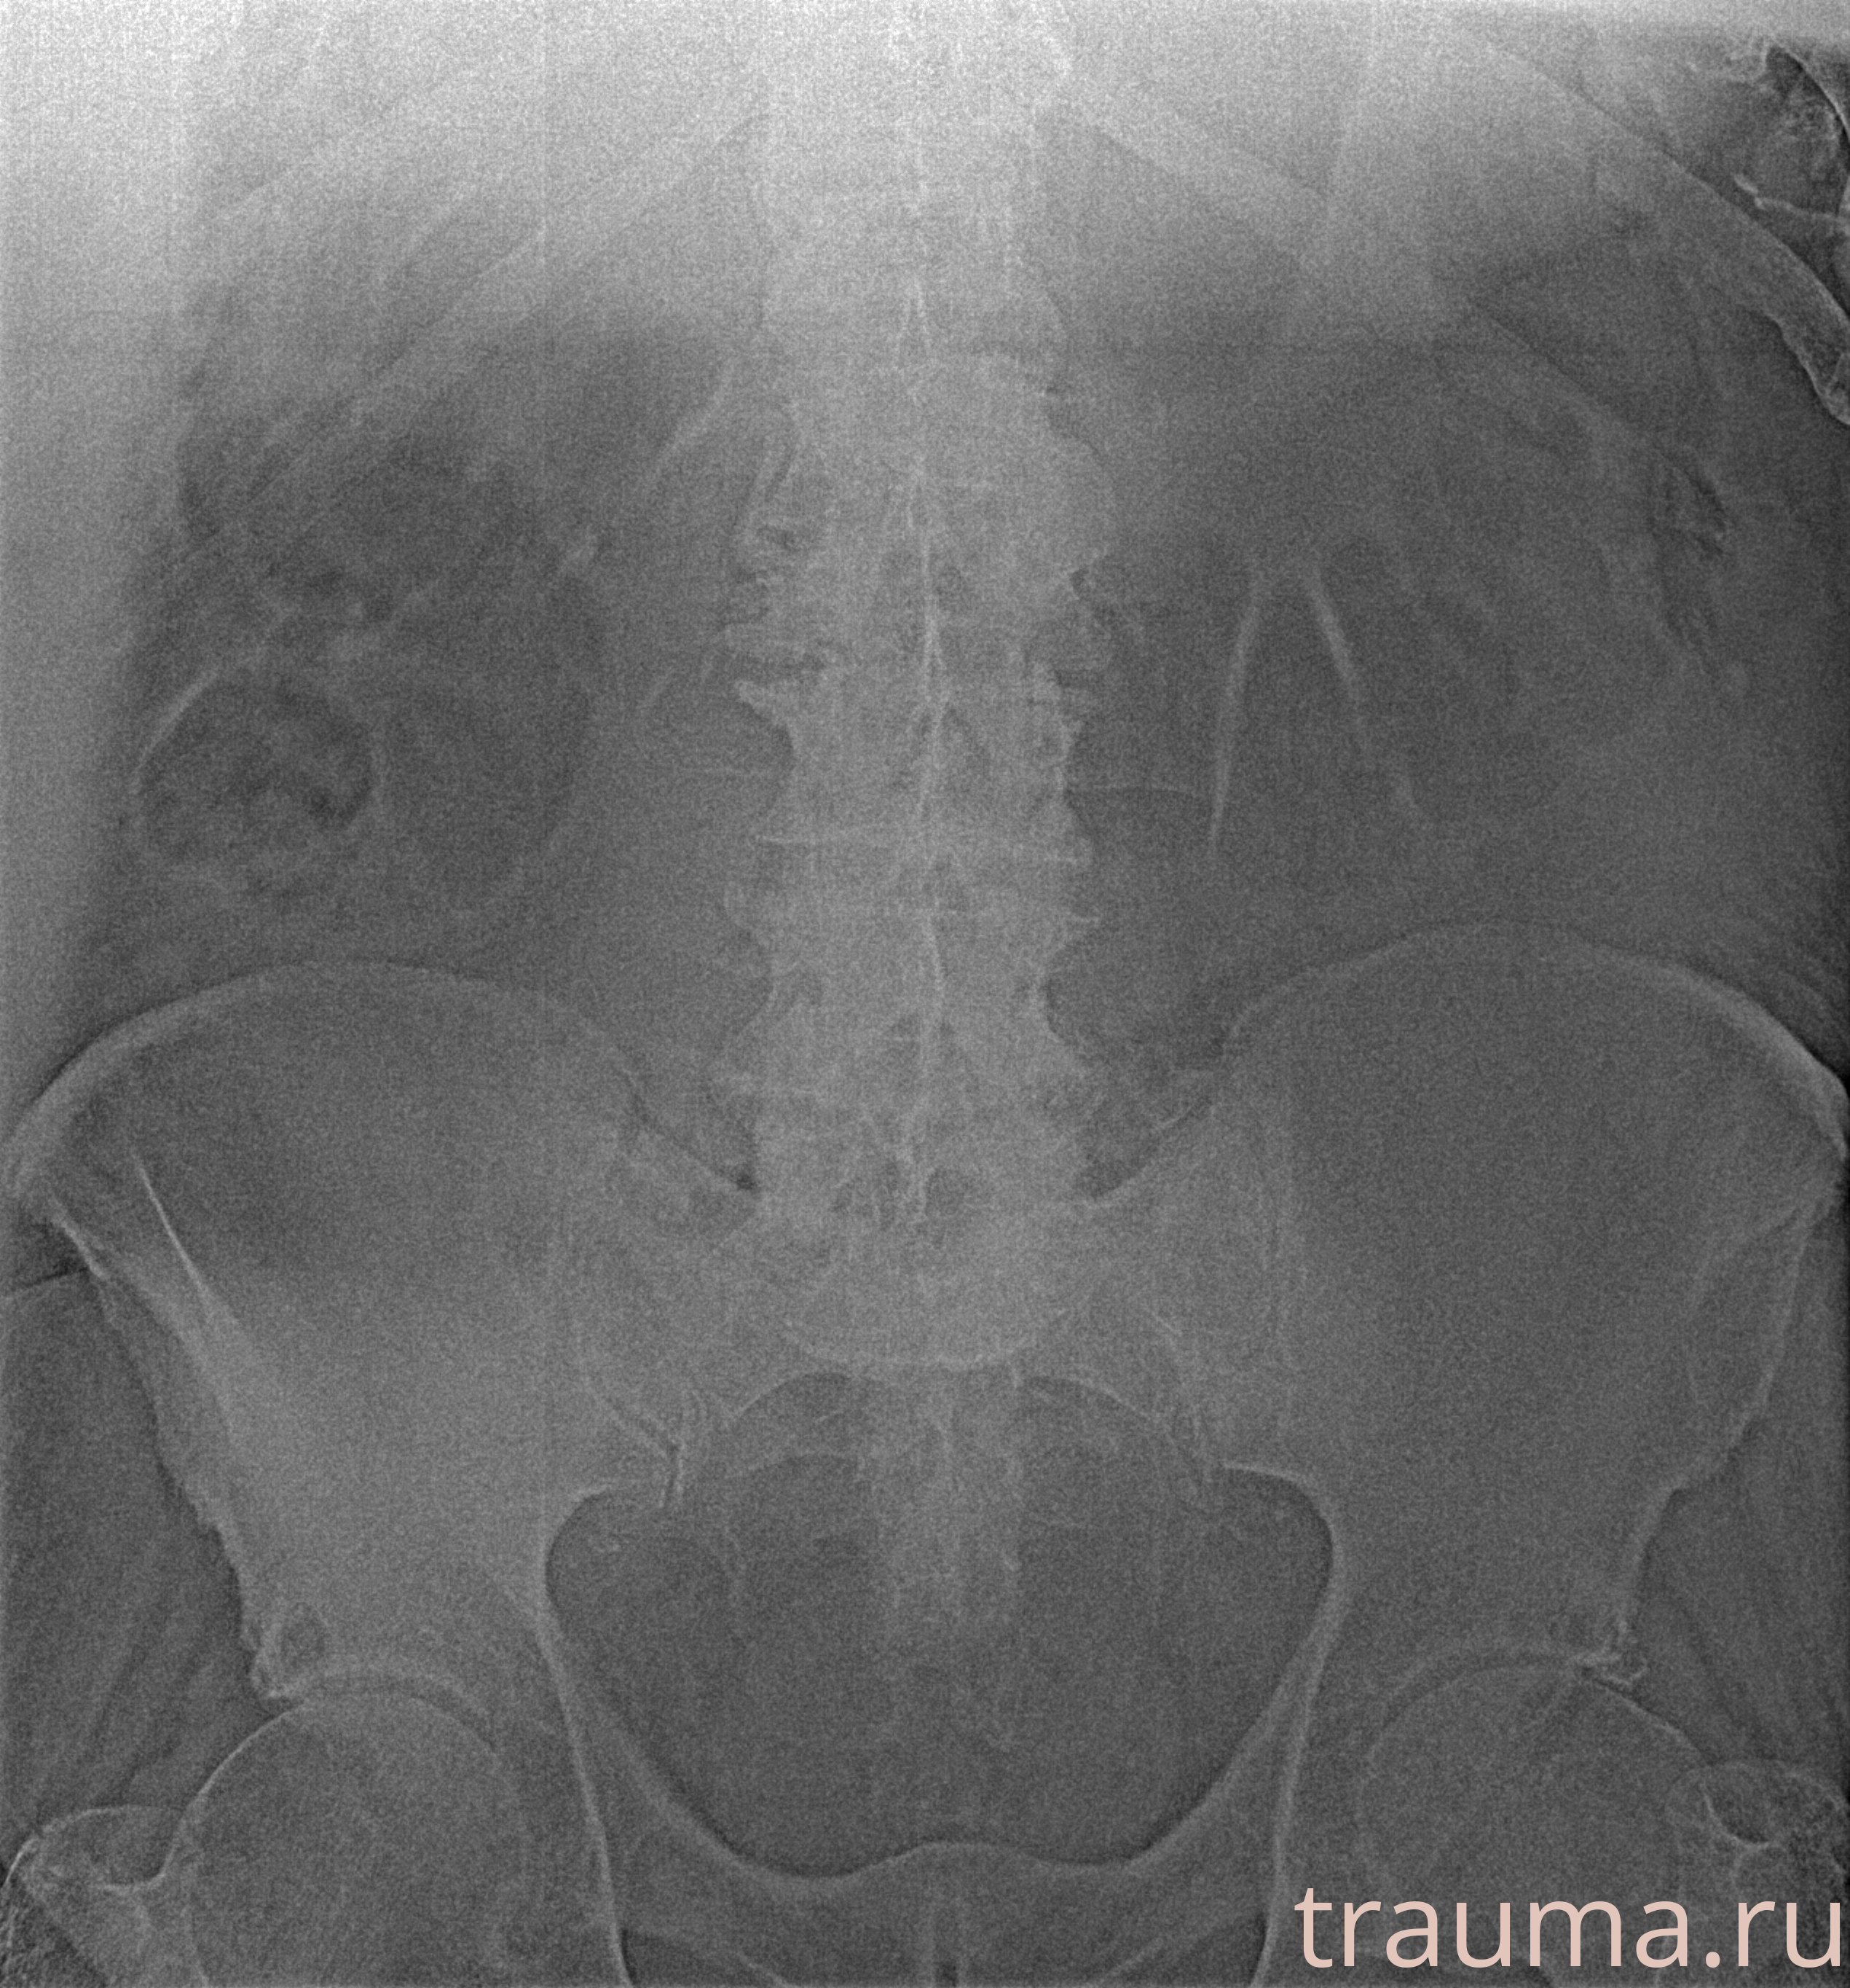

Рентген на дому: по вашему адресу приезжает врач-рентгенолог, травматолог-ортопед с мобильным рентгеновским аппаратом, проводит диагностику травмы или заболевания, делает необходимые рентгенограммы, дает рекомендации по дальнейшему лечению. Получить качественные снимки в домашних условиях возможно благодаря уникальной методике, разработанной МосРентген Центром для института  Склифосовского